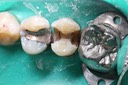

Alan Chinn #31 caries removal

Alan Chinn #31 prep